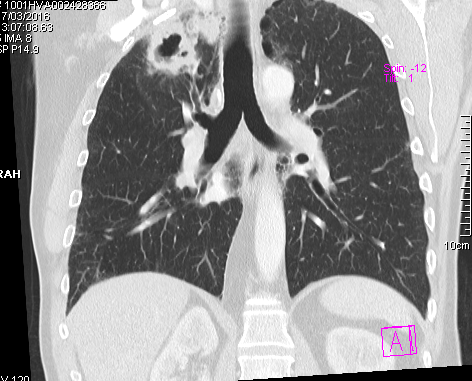

Obtenemos las siguientes imágenes en distintos planos:

Vemos que la estructura cavitada posee una pared muy gruesa, más típica de un proceso neoplásico, y una cavidad hipodensa. Confirmamos su localización en el lóbulo superior derecho y anterior. Descartamos proximidad a vasos y estructuras mediastinicas, así como invasión de la pared torácica. Y lo mas importante es que apreciamos que el bronquio principal mas proximal a la masa cavitada, el bronquio anterior del lóbulo superior derecho, se encuentra amputado cuando llega a la masa y no comunica con la cavidad del interior de la masa,